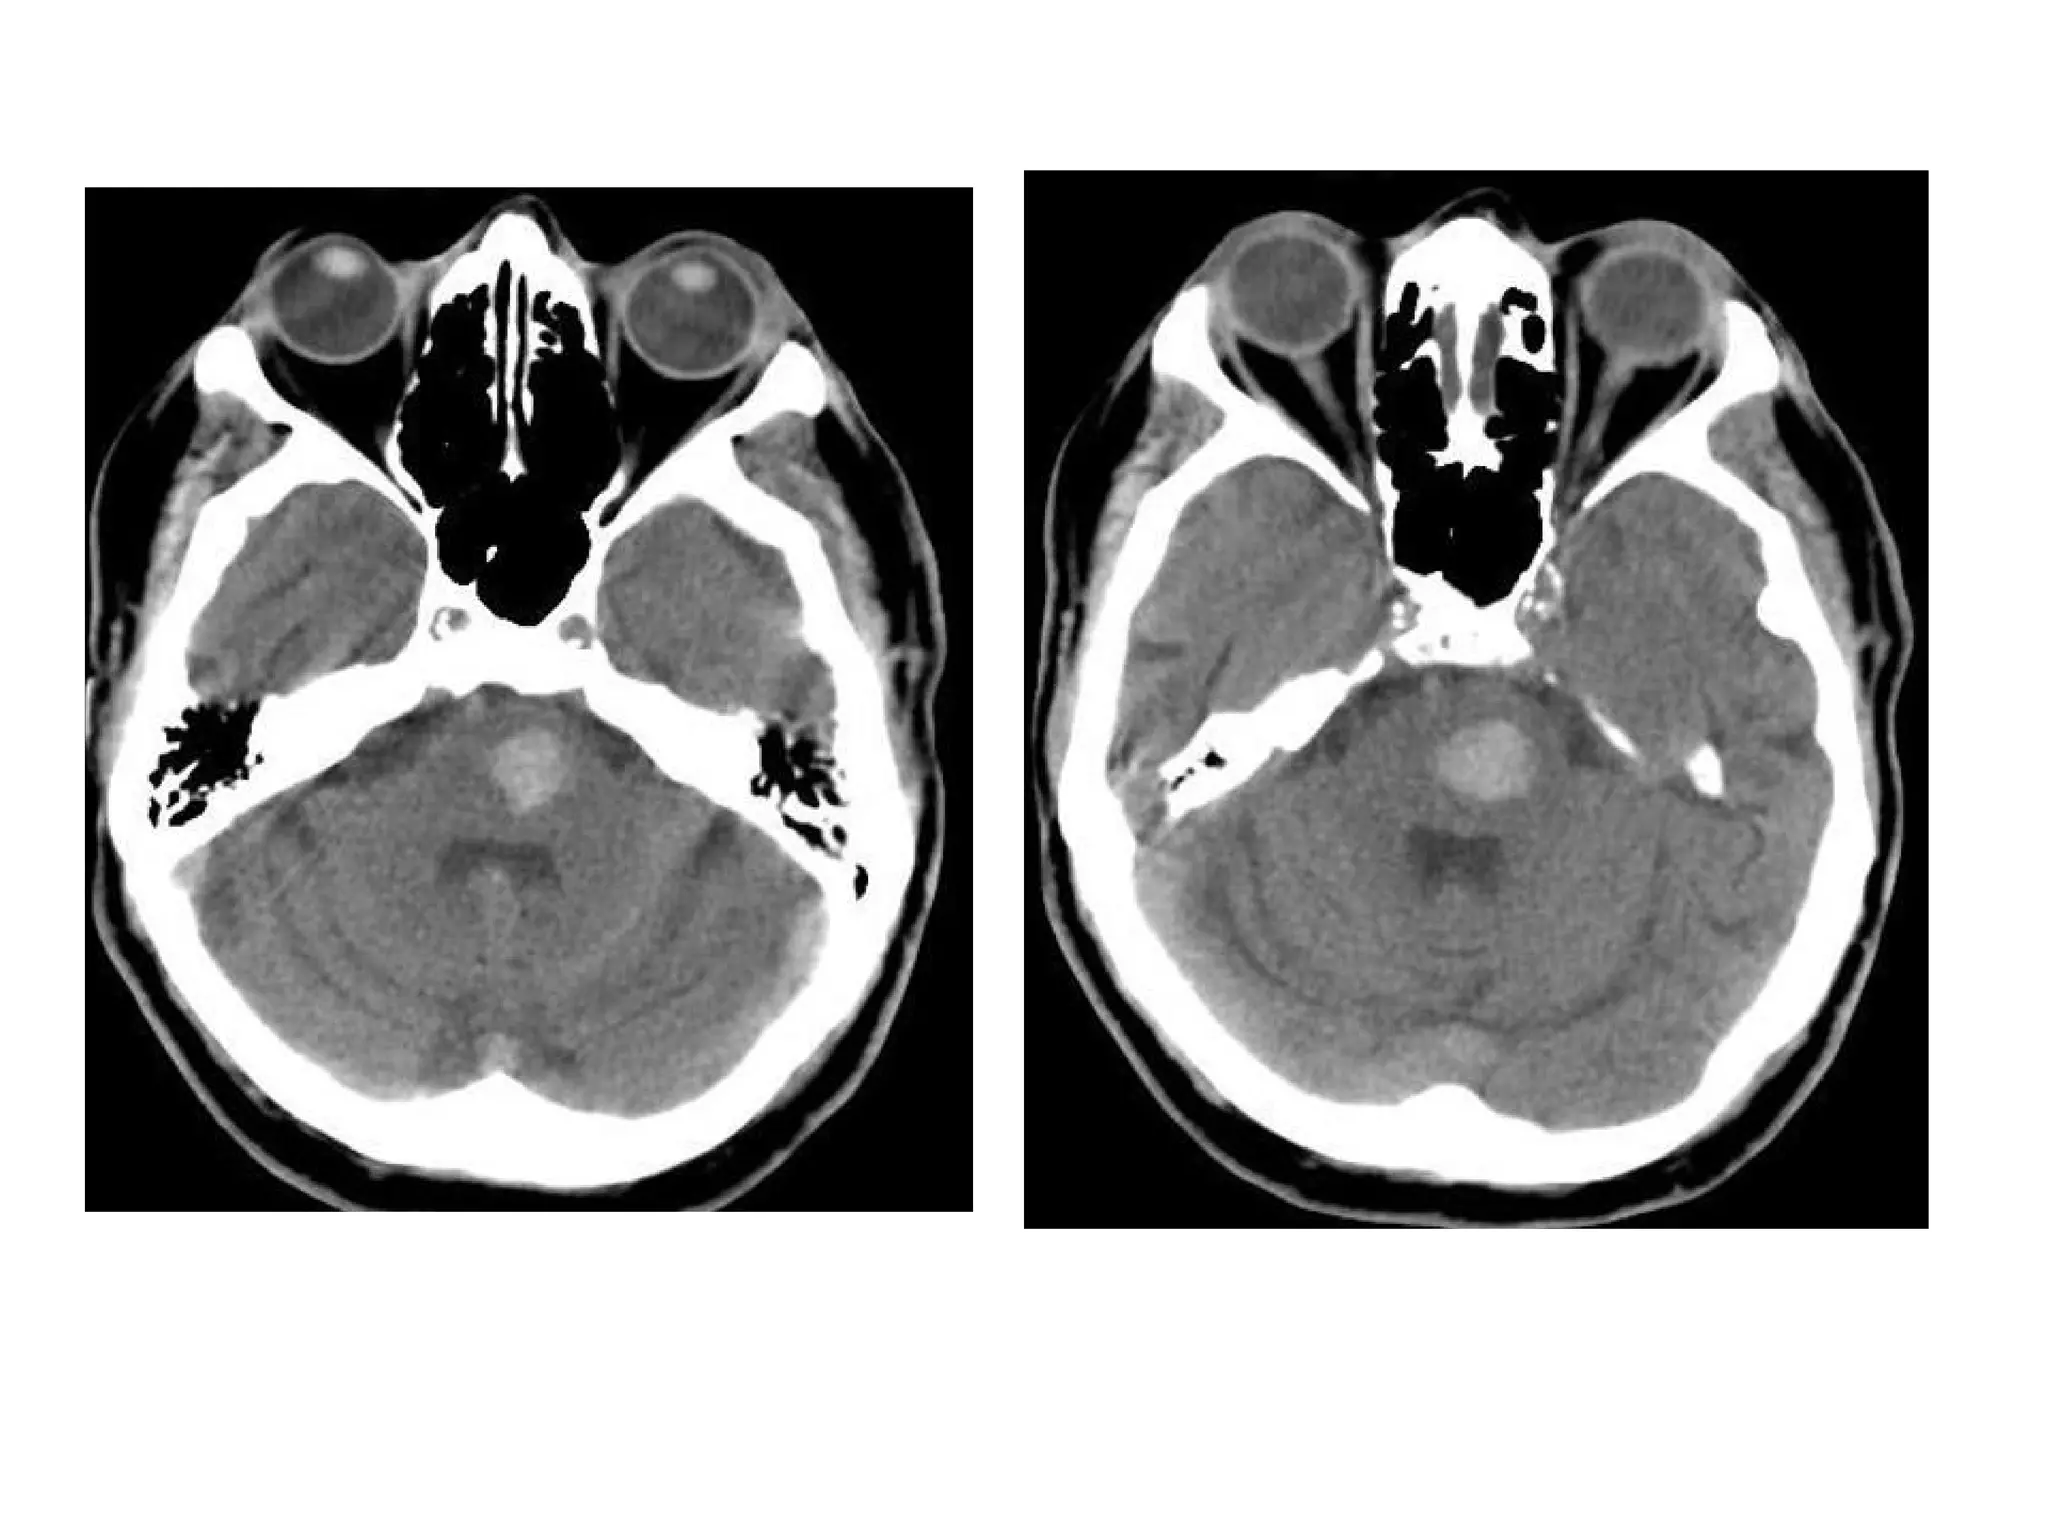

b) In the case of secondary hematomas :

-The radiographic features on both CT and MRI are

merely a summation of the features of a ischemic

infarct with superimposed cerebral hemorrhage

-The amount of hemorrhage relative the size of the

infarct can vary widely but usually it is possible to

identify significant areas of the brain which are

infarcted but not hemorrhagic

-This may not be the case if the hemorrhage is large

and the underlying infarct small

-By the time secondary hematomas form , the

underlying infarct should be easily seen

and will appear as a region of low attenuation

involving both the white matter and the

overlying cortex

-Hemorrhage is often patchy , scattered

throughout the infarcted tissue and usually

represents only a small component of the

abnormal tissue